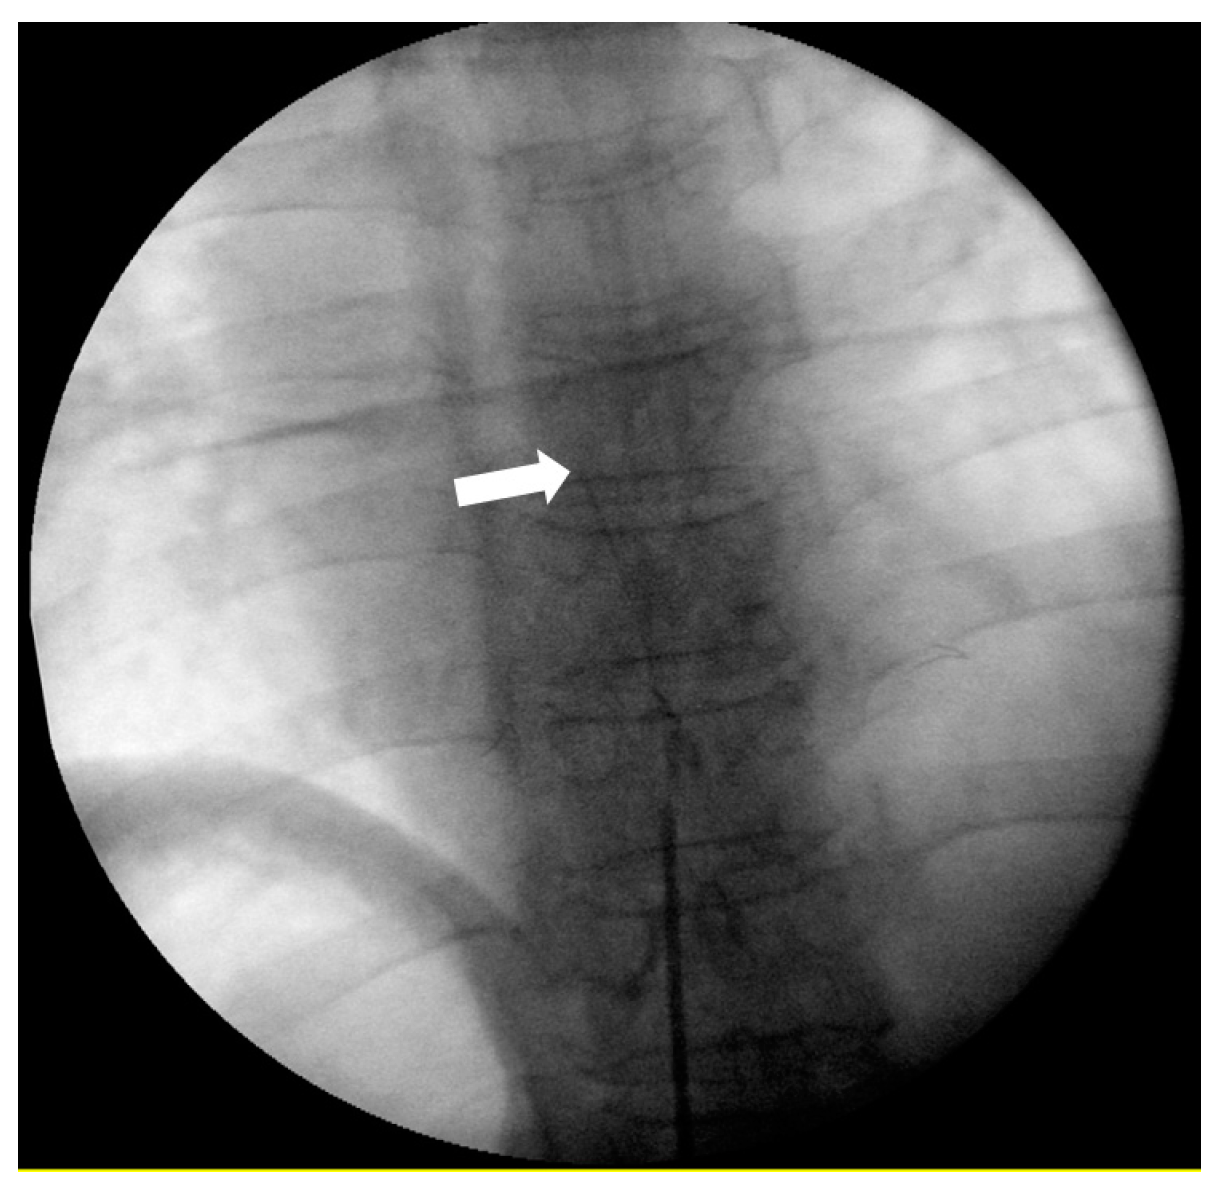

2.2. Procedure